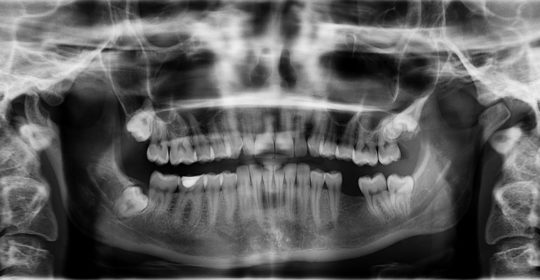

Having a tooth loss disturbs the natural balance between tooth and bone, the jaw will start to shrink as soon as your tooth is lost and gums recede. This, unfortunately, will start a cycle, your neighbouring teeth will weaken and yes, will cause more tooth loss. Due to the fact, there is space; the neighbouring teeth will naturally move towards that area making your teeth crooked and causing more orthodontic problems. With your jaw bone becoming weak your face may start to look different and you cheeks might look saggy.